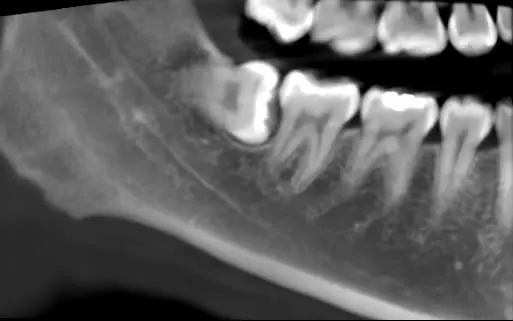

During one of my regular visits to the dentist, I was advised to remove my wisdom tooth as the X-ray showed that it was growing horizontally and could affect the tooth beside it.